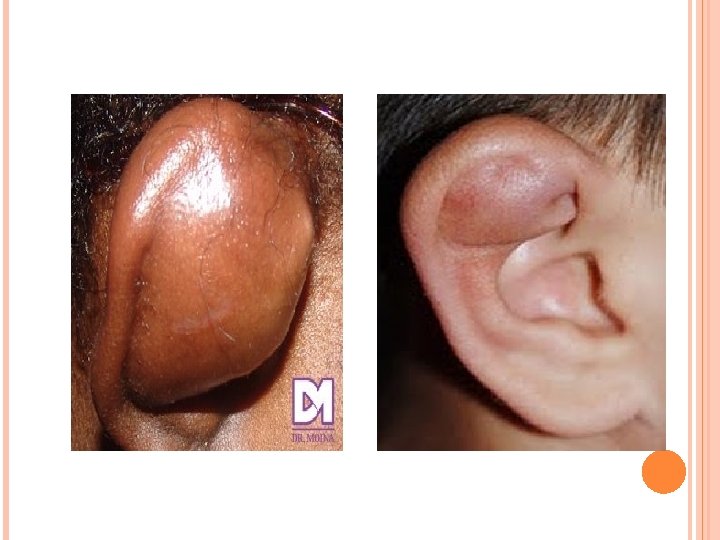

TRAUMATISMOS Por la rica vascularización conviene realizar una cuidadosa sutura, previo drenaje y antisepsia. Complicacion mas frecuente es el otohematoma. El cartílago se nutre por imbibición del pericondrio, un golpe tangencial sobre la piel del pabellón que esta adherida al pericondrio, puede separar a este del cartílago, formando una colección hemática que impide su nutrición llevándolo a la necrosis con la consiguiente deformación estética. El paciente presenta una tumefacción roja violácea del pabellón auricular. Se debe realizar una incisión evacuadora con la colocación de un drenaje y vendaje compresivo, prescribiéndose antibióticos, antiinflamatorio. Si hay arrancamiento total de la oreja se debe traer el fragmento en hielo para luego proceder a su reimplantación con cirugía microvascular.

HEMATOMA Es secundario a la ruptura de vasos entre el cartílago y el pericondrio, generalmente en la cara externa del pabellón. Generalmente secundarios a traumatismos (boxeadores), pero pueden ser espontáneos. Dejado evolucionar se puede producir la reabsorción del cartílago produciendo una deformación llamada oreja de "coliflor". Tratamiento Drenar el hematoma, si es pequeño con punción y si es grande con incisión. Posteriormente aplicar compresión con vendaje externo que adose la piel al cartílago subyacente.